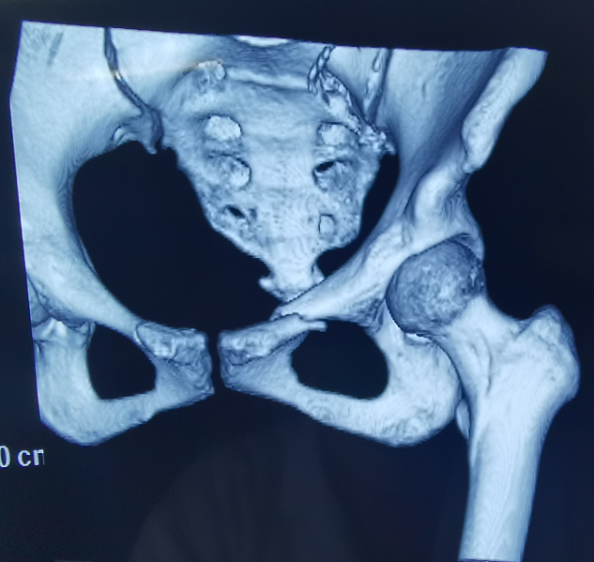

患者为22岁年轻女性,因车祸致骨盆骨折。骨盆骨折是一种重大的创伤,古板手术方法需要较量大的切口,并且骨盆内有大宗重大血管和神经,手术难度和危害极大,是许多骨科医生的禁区。

我国自主研发的天玑?骨科手术机械人,是针对骨骼硬组织的先进手艺,已经获得国际认可,能够开展脊柱全节段 (颈椎、胸椎、腰椎、骶椎) 疾病、骨盆和四肢等骨折、骨肿瘤以及枢纽导航等手术。相比古板手术,机械人辅助手术具有手术创伤小、出血少、并发症少、康复快的优势。同时,由于不需通过重复透视来确定置钉位置,从而能镌汰术中辐射,大大降低患者辐射危害,且手术历程中,由机械人与主刀医师配合完成手术,大大增添了手术清静性。